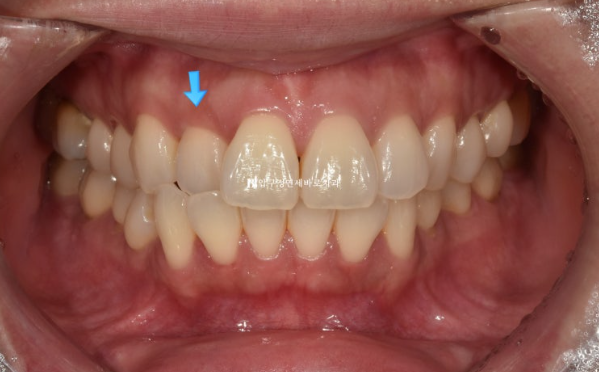

23.10

The blue arrow shows the front teeth biting in the wrong direction.

Because the teeth that bite in the wrong direction are positioned backward, the two central incisors appear relatively protruded.